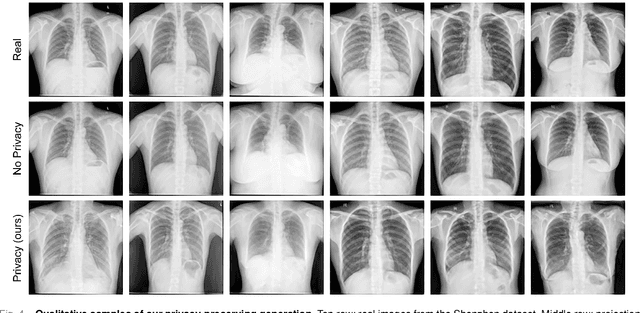

Abstract:Generative Adversarial Networks (GANs) have demonstrated their ability to generate synthetic samples that match a target distribution. However, from a privacy perspective, using GANs as a proxy for data sharing is not a safe solution, as they tend to embed near-duplicates of real samples in the latent space. Recent works, inspired by k-anonymity principles, address this issue through sample aggregation in the latent space, with the drawback of reducing the dataset by a factor of k. Our work aims to mitigate this problem by proposing a latent space navigation strategy able to generate diverse synthetic samples that may support effective training of deep models, while addressing privacy concerns in a principled way. Our approach leverages an auxiliary identity classifier as a guide to non-linearly walk between points in the latent space, minimizing the risk of collision with near-duplicates of real samples. We empirically demonstrate that, given any random pair of points in the latent space, our walking strategy is safer than linear interpolation. We then test our path-finding strategy combined to k-same methods and demonstrate, on two benchmarks for tuberculosis and diabetic retinopathy classification, that training a model using samples generated by our approach mitigate drops in performance, while keeping privacy preservation.